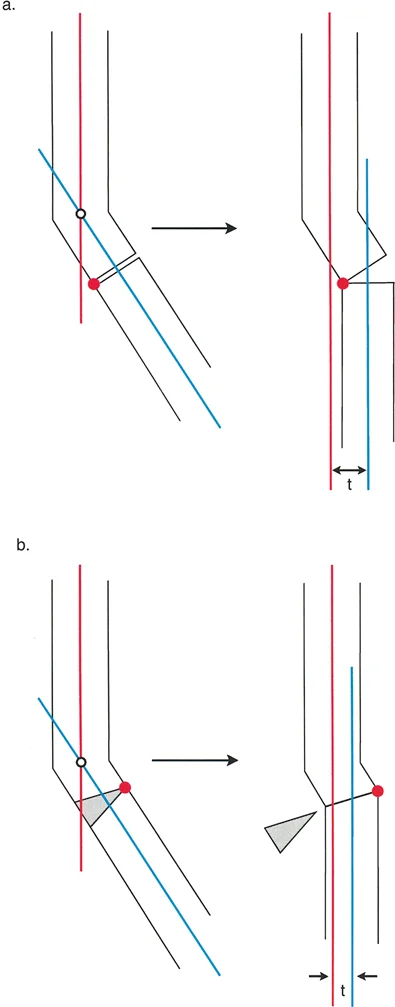

تثبيت المسمار الداخلي بمساعدة المثبت الخارجي (FAN) هو تقنية جراحية حديثة تجمع بين دقة المثبت الخارجي المؤقت واستقرار المسمار الداخلي الدائم، مما يوفر تصحيحًا فائقًا لتشوهات العظام المعقدة مع راحة فورية للمريض وتعافٍ أسرع.

الخلاصة الطبية السريعة: تثبيت المسمار الداخلي بمساعدة المثبت الخارجي (FAN) هو تقنية جراحية حديثة تجمع بين دقة المثبت الخارجي المؤقت واستقرار المسمار الداخلي الدائم، مما يوفر تصحيحًا فائقًا لتشوهات العظام المعقدة مع راحة فورية للمريض وتعافٍ أسرع.